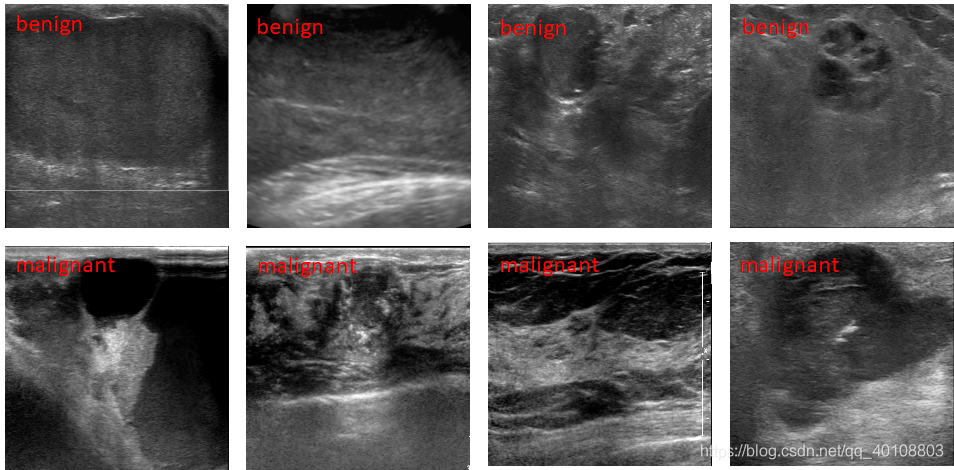

5.添加文字标注。

6.图片另存。(jpg、png、tif)